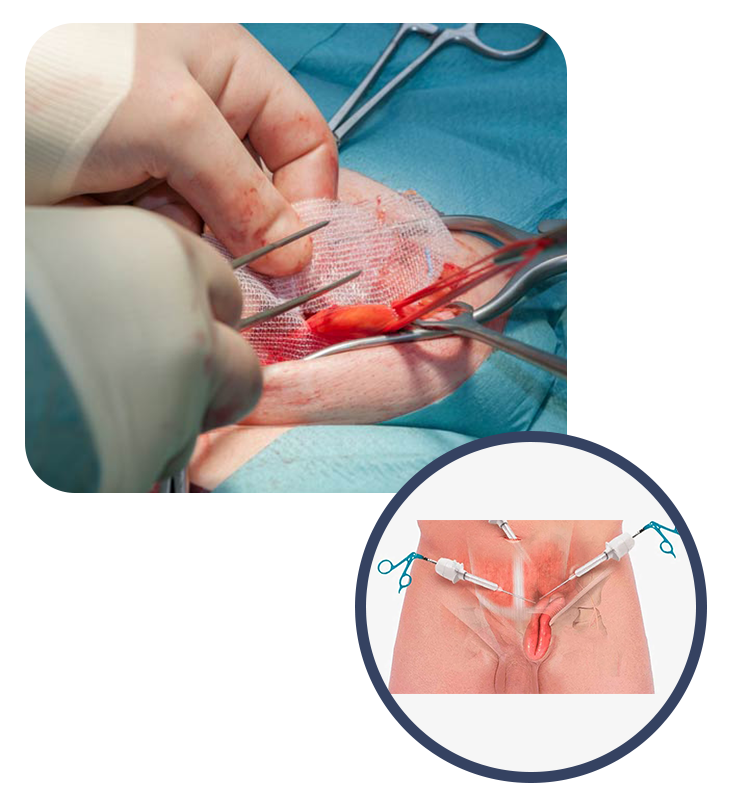

Una hernia inguinal ocurre cuando los tejidos, comúnmente parte del intestino, se producen a través de una abertura en la pared abdominal en la región de la ingle. Esta abertura a menudo se forma en un área debilitada de los músculos abdominales. El síntoma principal es una protuberancia en la ingle que puede ser visible o palpable al tocarla. Esta protuberancia puede ser más evidente al realizar esfuerzos físicos, como levantar objetos pesados. A menudo, se acompaña de molestias o dolor en la zona. Existen dos tipos principales: directas e indirectas. Las hernias directas tienden a ocurrir en áreas debilitadas de la pared abdominal, mientras que las hernias indirectas a menudo se deben a una abertura persistente en el conducto inguinal, una estructura natural en el desarrollo fetal. El diagnóstico implica un examen físico y, a veces, estudios de imágenes como ultrasonido o tomografía computarizada. El tratamiento consiste en la cirugía para reparar la abertura y devolver los tejidos protruidos a su lugar. La cirugía a menudo se recomienda para evitar complicaciones potenciales, como el atrapamiento de tejidos, que puede ser doloroso y, en casos raros, amenazar la irrigación sanguínea.